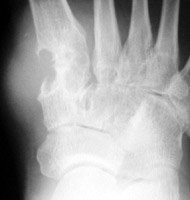

Gout: AP- Erosions 1st MTP joint with tophiGout: AP- Erosions 1st MTP joint with tophiTophaceus Gout: LateralTophaceus Gout: APGOUT is caused by monosodium urate or uric acid crystal deposition within cartilage, bone, or periarticular tissues.

First metatarsophalangeal joint is most commonly affected, followed by the first interphalangeal joint and tarsometatarsal joints. Posterior calcaneal involvement has also been noted. The majority of first presentations are monoarticular. Bilateral and symmetric or asymmetric polyarticular involvement may be present within any of the foot joints.

Acute, episodic soft tissue swelling may represent the earliest radiographic sign. Later, sharp, round or oval marginal joint erosions with sclerotic borders are classically seen with gout. These findings most commonly occur along the dorsum of the foot. Associated soft tissue tophi or intraosseous nodules may be present. "Overhanging margin" occur where the bone resorbs beneath a tophaceous nodule. Joint spaces are usually preserved, but ankylosis may rarely occur with advanced stages of gout. The aforementioned findings may be in different stages of progression with any given patient.